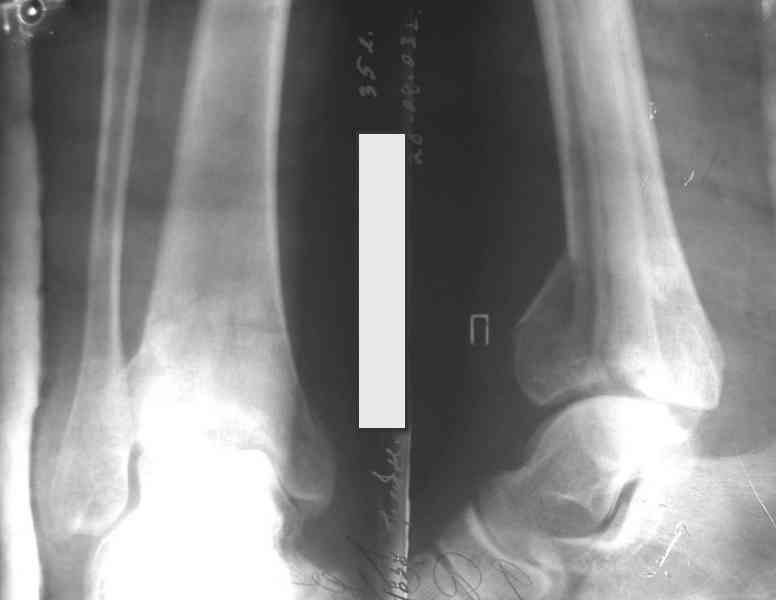

На рентгенограммах типичный перелом пилона по типу С-3. есть опыт до 100 открытых опреаций у нас в клинике. 20 примерно в год. Принцип один -все внутрисуставные переломы нуждаются в открытой репозиции и внутренней стабильной фиксации. При поступлении КТ не надо, так как получается только нагромождение костей. Истинной картины нет. Главное восстановить длину малоберцовой кости - это ключ к успеху. При поступлении меньше всего надо думать о сосудистых расстройствах, т.к. сама операция и репозиция даже сначала частичная даёт улучшение сосудитых нарушений. Причём очень быстро. Операция в 2этапа. При поступлении доступ позади наружной лодыжки, причём обязательно. После этого репозиция малоберцовой кости и фиксация пластиной 1/3 трубки под винт 3,5. Дренаж и любой аппарат наружной фиксации. Затем после спадения отёка на 5-7-10 день аппрат снимается и дугообразный разрез спереди от медиальной лодыжки 10-12 см. Главной чтобы расстояние между 1 и вторым разрезом было не меньше 7-8 см. Тогда не будет некрозов лоскутов. Таранная кость используется как матрица на неё укладываются отломки и фиксируются пицами. Ренг-контроль. Отломки лежат все отдельно, но ничего не высыпется. При переломах С-3 всегда нужна костная пластика (из крыла). Фиксация пластиной лист клевера простой или LCP. Гипс не нужен. Дренаж до 48 часов. Операция длится 3-4 часа обязательно без жгута. Посылаю примерно такой же случай.

Ещё есть одна проблема когда есть перелом малоберцовой кость, то всё ясно. А когда малоберцовая кость не повреждена, то сразу накладывается аппрат наружной фиксации при поступлении, чтобы как бы перерастянуть отломки и главное убрать вальгусное или варусное смещение, а потом на 5-7 день открыто большеберцовая кость восстанавливается и фиксируется пластиной. С уважением Дрягин